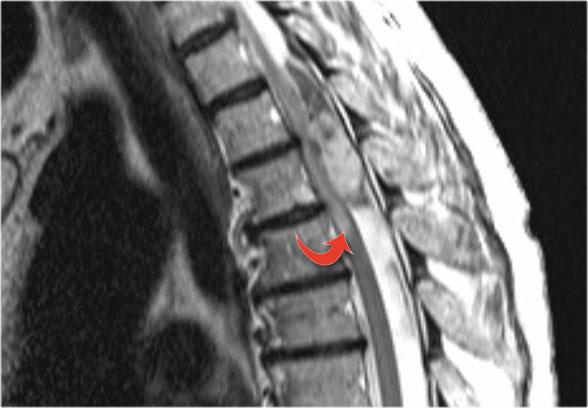

Hình ảnh mặt phẳng đứng dọc cho thấy một đoạn dài tăng tín hiệu trên chuỗi xung T2W.

Hình ảnh mặt phẳng ngang cho thấy phần lớn tủy sống bị tổn thương.

Đây là hình ảnh của bệnh nhân nam 31 tuổi với các triệu chứng đau đầu, rối loạn đi tiểu, bí tiểu, mức cảm giác tại C3.

Phân tích dịch não tủy (CSF) cho thấy 400/3 tế bào (không có dấu hiệu nhiễm trùng) và nồng độ protein tăng nhẹ.

Hình ảnh cho thấy bệnh lý tủy đoạn dài với tổn thương toàn bộ mặt cắt ngang.

Không có phù nề và không có ngấm thuốc tương phản từ.

Hình ảnh không điển hình cho xơ cứng rải rác (MS) hay u, do đó chúng tôi nghĩ đến ATM – viêm tủy cắt ngang cấp tính.

Đây là hình ảnh của một trường hợp TM điển hình.

Có tăng tín hiệu đa đoạn trên STIR và chuỗi xung T2W kèm theo phù nề nhẹ.

Phần lớn tủy sống trên đường kính ngang bị tổn thương.

Không có ngấm thuốc tương phản từ, đây thường là đặc điểm thường gặp trong TM.

Đôi khi có thể thấy ngấm thuốc dạng vá không đều.

Khi có ngấm thuốc tương phản từ, việc phân biệt TM với u tế bào hình sao (astrocytoma) có thể rất khó khăn.